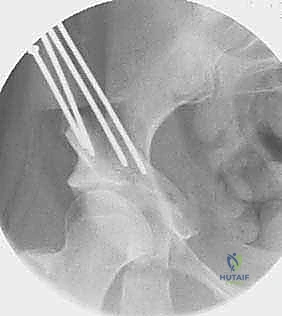

2. سلسلة قطع العظام (The 5 Osteotomies)

يكمن سر نجاح جراحة PAO في إجراء خمسة قطوع عظمية منفصلة حول الحُق، لتحريره بالكامل عن باقي الحوض، مع ترك العمود الخلفي سليماً كدعامة أساسية.

القطع الأول: القطع الإسكي غير المكتمل (Incomplete Ischial Osteotomy)

باستخدام إزميل خاص ذو زاوية (Angled Osteotome)، يتم إجراء قطع في عظم الإسك أسفل الحُق مباشرة (في الأخدود تحت الحُقي). يتم هذا القطع بتوجيه الأشعة السينية (Fluoroscopy) لضمان عدم اختراق المفصل. يحرص الدكتور هطيف على إبعاد العصب الوركي والأوعية السدادية بأمان تام.